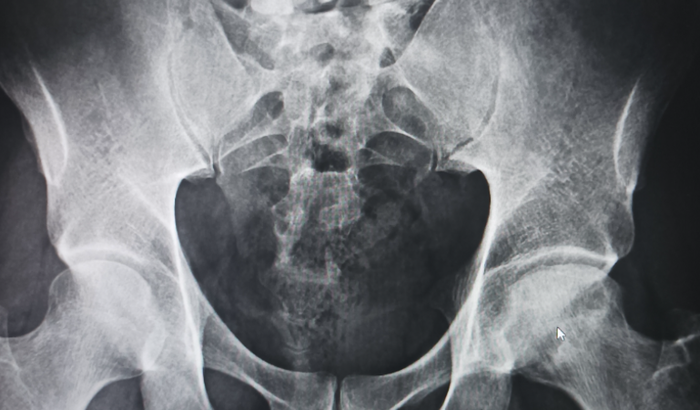

SOU JASON RIBEIRO, TENHO 38 ANOS. No ano passado comecei sentir dores nas costas , fui ao médico tomava só injeção e não passava .Um dia com fortes dores procurei um otorpedista, fiz uma ressonância e o médico falou que eu estava com hérnia de disco!! Mas as dores foram descendo para a virilha e pernas 😔!! Fortes dores me incomodavam, tive que fazer outra ressonância do quadril e foi quando tudo na minha vida mudou, estou com FÊMUR NECROSADO 😔!! O médico falou que preciso urgentemente fazer uma cirurgia na cabeça do fêmur para colocar uma prótese, o custo dessa cirurgia é em torno de 40.000.00 á 45.000.000!!Tudo que mais quero é minha saúde de volta, preciso trabalhar pois sou pai de família, minha esposa e meus filhos precisam de mim!! Venho aqui pedir ajuda, meus filhos são tudo que tenho e quero cuidar deles com saúde!! Tenho uma linda menina que vai fazer 10 anos esse mês de março e ela fala que esse é o presente que ela mais quer, vê seu pai bem!! 🙏🏽😞Também tenho um menino de 1 ano e 4meses!! Quem puder me ajudar e compartilhar minha história!! Agradeço🙏🏽